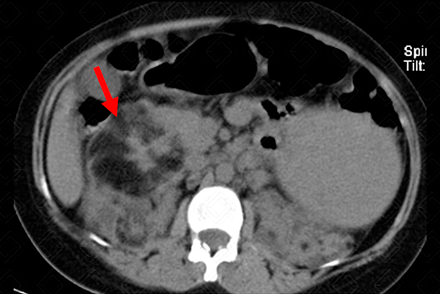

Texto alternativo para a imagem Créditos: Dra. Elazir Mota - Rio de Janeiro/RJ

Descrição da figura: Lesão expansiva, heterogênea, com predomínio de conteúdo gorduroso, no pólo superior do rim direito, medindo 8,3 x 7,6 cm, compatível com angiomiolipoma (seta vermelha).

• Tomografia computadorizada do abdome: Lesão renal, bem definida, heterogênea, predominantemente hipodensa, com densidade de gordura, em geral inferior a -10 UH (f igura acima);